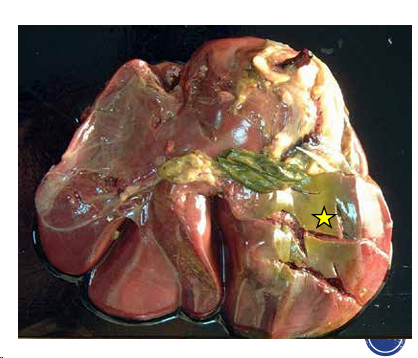

Melanosis maculosa congenita

- NO patologica

- Melanina localizaciones no habituales

- Se decomisa aunque no sea problematica

- En rumiantes o en cerdo

- Generalmente en pulmon pero puede aparecer en otros organos

- Manchas negras

Aspecto macroscópico: Manchas poligonales negras:

- En pleura, pericardio

- Calsulas hepatica

- Intima de la aorta

Acaba involucionando/Involución congénita si crece